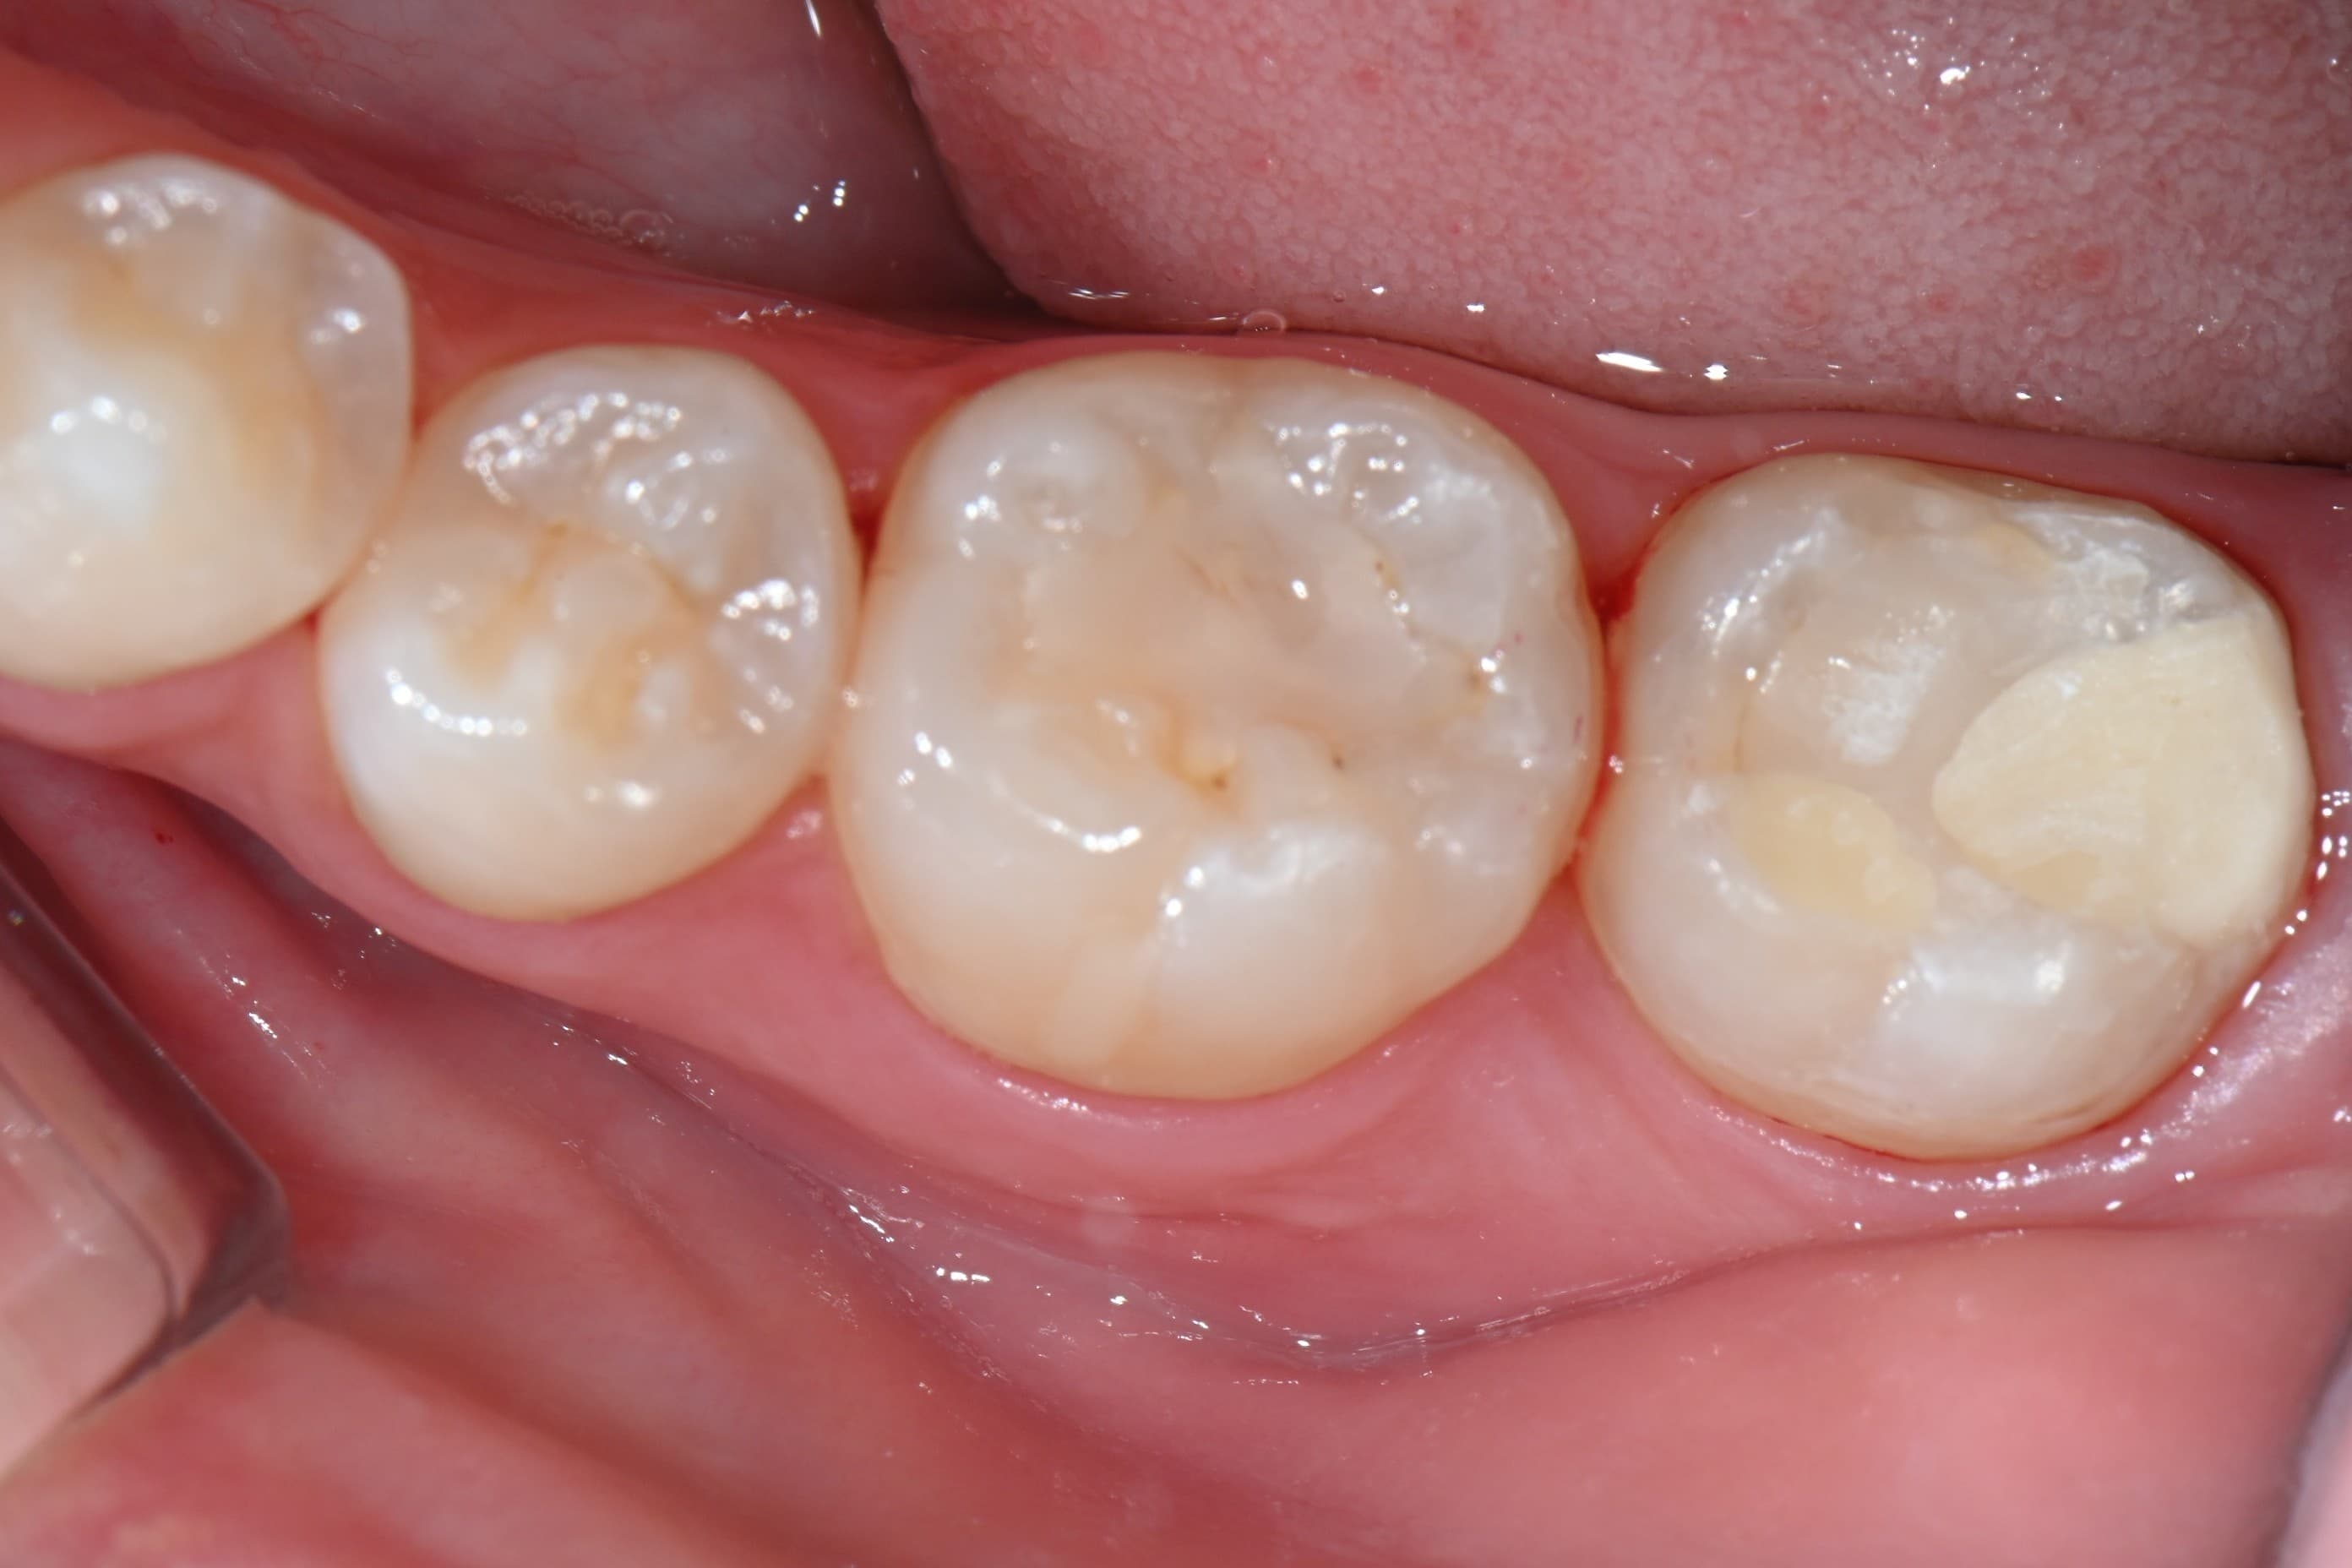

치료 전 상태

어금니에 충치가 진행된 상태입니다. 치아 표면에 충치로 인한 변색과 손상이 확인됩니다.

치료 완료

충치를 완전히 제거하고 자연 치아 색상의 레진으로 수복했습니다. 치아 형태가 깔끔하게 회복되었습니다.